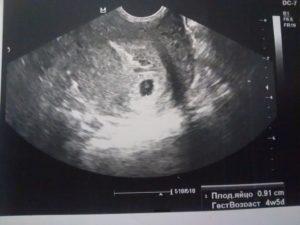

Плодное яйцо можно увидеть начиная с 3 недели. Оно представляет собой образование темного цвета, круглой формы, окруженное тонкой оболочкой, до 5 мм в диаметре. Сам эмбрион в этот период с помощью УЗИ увидеть нельзя, он слишком маленький. Различимым на экране он становится в начале 2 месяца. Это объект продолговатой формы, который закрепляется в плодном яйце при помощи пуповины.

Многие беременные девушки или будущие мамы хотят узнать, когда в плодном яйце появляется эмбрион (точнее говоря, когда можно будет увидеть его на УЗИ). Чтобы зародыш смогли обнаружить ультразвуковые сканеры, само плодное яйцо должно быть достаточно большим.

Когда появляется эмбрион в плодном яйце?

Впервые эмбрион можно рассмотреть примерно на пятой неделе беременности. Именно на этот срок обычно и назначают врачи первое УЗ-исследование. Диаметр плодного яйца к этому времени составляет, как правило, около 7 миллиметров. А непосредственно зародыш имеет размер около 2,5 миллиметров.

Но если на этом первом УЗИ ничего увидеть не удалось, отчаиваться не стоит – каждая беременность протекает индивидуально. И подождав ещё пару недель, девушка в положении наверняка впервые увидит своего будущего малыша.

Увидеть беременность на УЗИ можно уже с трех – четырех недель, когда плодное яйцо достигает трех миллиметров приблизительно. Далее с появлением и ростом эмбриона размеры его увеличиваются.

В пять недель – это семь миллиметров, а в восемь – двадцать семь и более миллиметров.